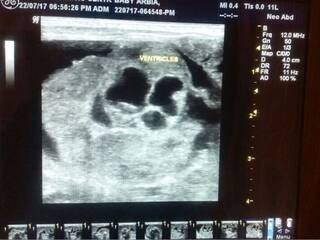

ठाणे : बाळाच्या पोटात गर्भ आढळणं ही बाब दुर्मिळ आहे. ठाण्यातील मुंब्र्यामध्ये एका दाम्पत्याच्या अर्भकाबाबत ही घटना घडली आहे. चार दिवसांच्या बाळाच्या पोटात आढळलेला गर्भ शस्त्रक्रियेद्वारे काढून टाकण्यात आला. चार दिवसांपूर्वी मुंब्र्यातील दाम्पत्याला मुलगा झाला. त्याचं पोट फुगीर असल्याचं डॉक्टरांच्या निदर्शनास आलं. काही चाचण्यांनंतर हा प्रकार डॉक्टरांच्या लक्षात आला. या प्रकाराला ‘पिट्स इन पिटू’ असं संबोधलं जातं. बाळाच्या पोटातील गर्भसदृश्य गाठ काढून त्याचे प्राण वाचवण्यात डॉक्टरांना यश आलं आहे. ठाण्याच्या मानपाडा भागातील टायटन रुग्णालयात जवळपास अडीच तास हे ऑपरेशन चाललं. बाळ गर्भात असल्यापासूनच रेडिओलॉजिस्ट डॉ. भावना थोरात यांनी याबाबत पालकांना कल्पना दिली होती. आता शस्त्रक्रिया करुन अविकसित गर्भाचा सूक्ष्म अंश काढण्यात आला.